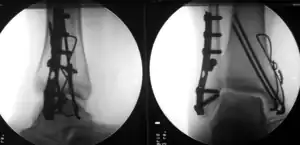

Treatment

Treatment of ankle fractures is dictated by the stability of the ankle joint. Certain fractures patterns are deemed stable, and may be treated similar to ankle sprains. All other types require surgery, which is usually performed with permanently implanted metal hardware that holds the bones in place while the natural healing process occurs. A cast or splint will be required to immobilize the ankle following surgery.[1]